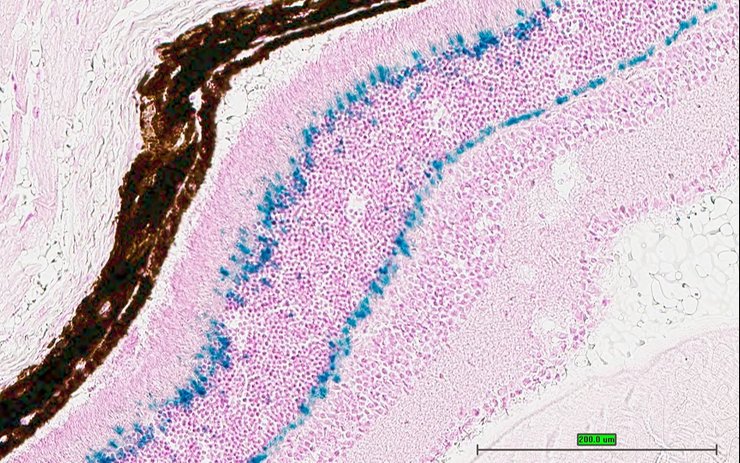

Specimen UC Davis_1877111: postnatal adult; Cabp4tm1.1(KOMP)Vlcg/Cabp4+ (more )

Structure Level Pattern Image Note

TS28: eye Present UC Davis_1877111

Specimen UC Davis_1877112: postnatal adult; Cabp4tm1.1(KOMP)Vlcg/Cabp4+ (more )

TS28: eye Present UC Davis_1877112

Specimen UC Davis_1877114: postnatal adult; Cabp4tm1.1(KOMP)Vlcg/Cabp4+ (more )

TS28: eye Present UC Davis_1877114

Specimen UC Davis_1877115: postnatal adult; Cabp4tm1.1(KOMP)Vlcg/Cabp4+ (more )

TS28: eye Present UC Davis_1877115